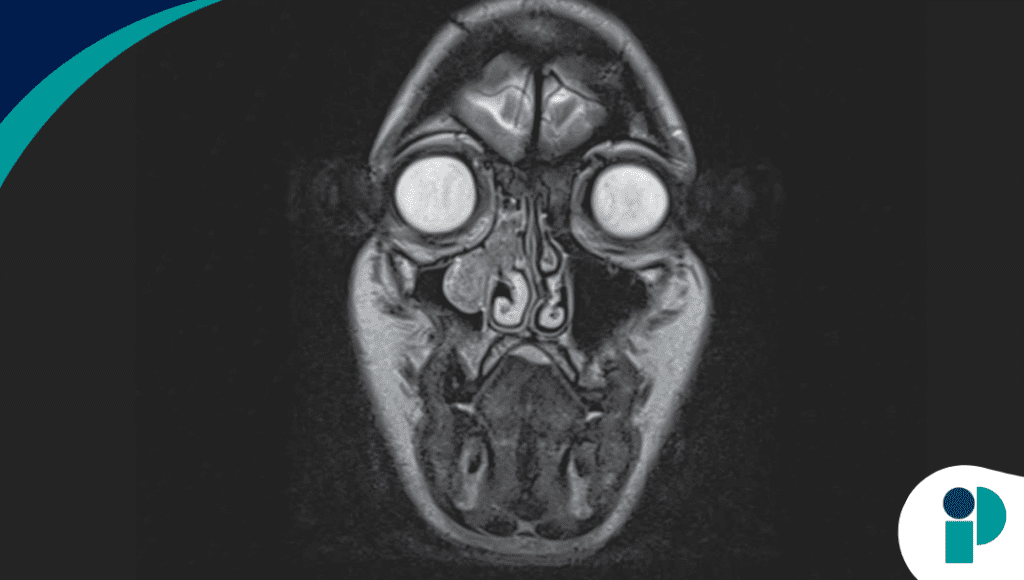

Estudios posteriores, incluyendo tomografía por emisión de positrones y resonancia magnética, mostraron un tumor hipermetabólico, altamente celular y con realce intenso tras la administración de contraste, compatible con una neoplasia activa. Otros hallazgos incidentales en hígado, páncreas y glándula suprarrenal resultaron benignos.

El análisis histopatológico confirmó el diagnóstico de un neuroblastoma olfatorio de bajo grado, una neoplasia neuroendocrina rara que habitualmente se origina en la región superior de la cavidad nasal. En este caso, la localización en el seno maxilar representó una presentación anatómica inusual. El comité multidisciplinario recomendó tratamiento quirúrgico seguido de radioterapia adyuvante.